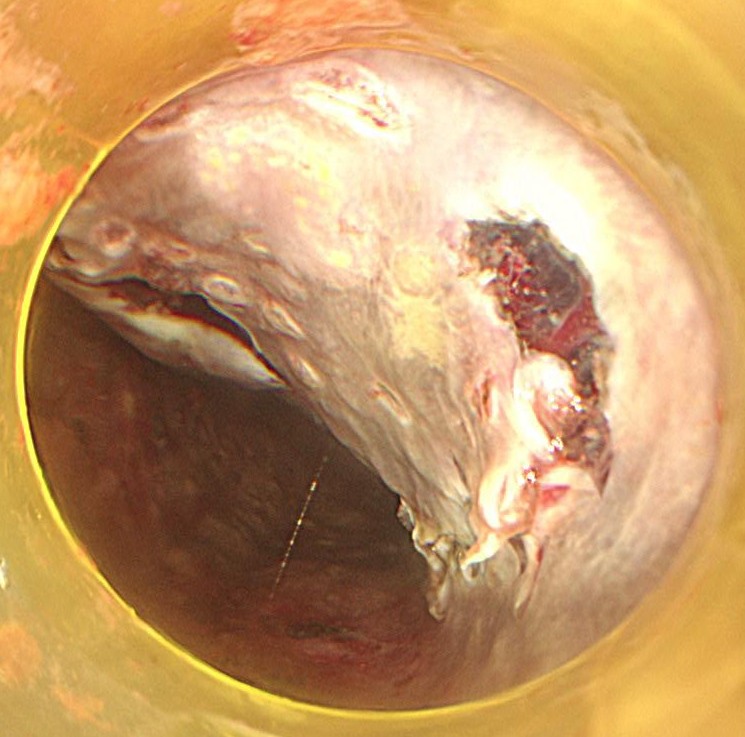

粘膜下層剥離術を開始します。粘膜下局注はムコアップを使用しています。デュアルナイフ1.5mmでスイフトコアグ30で少しずつ剥離していきます。